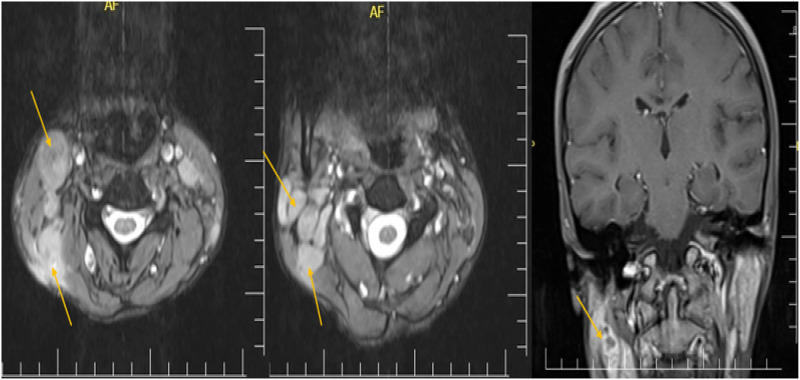

Abstract Image